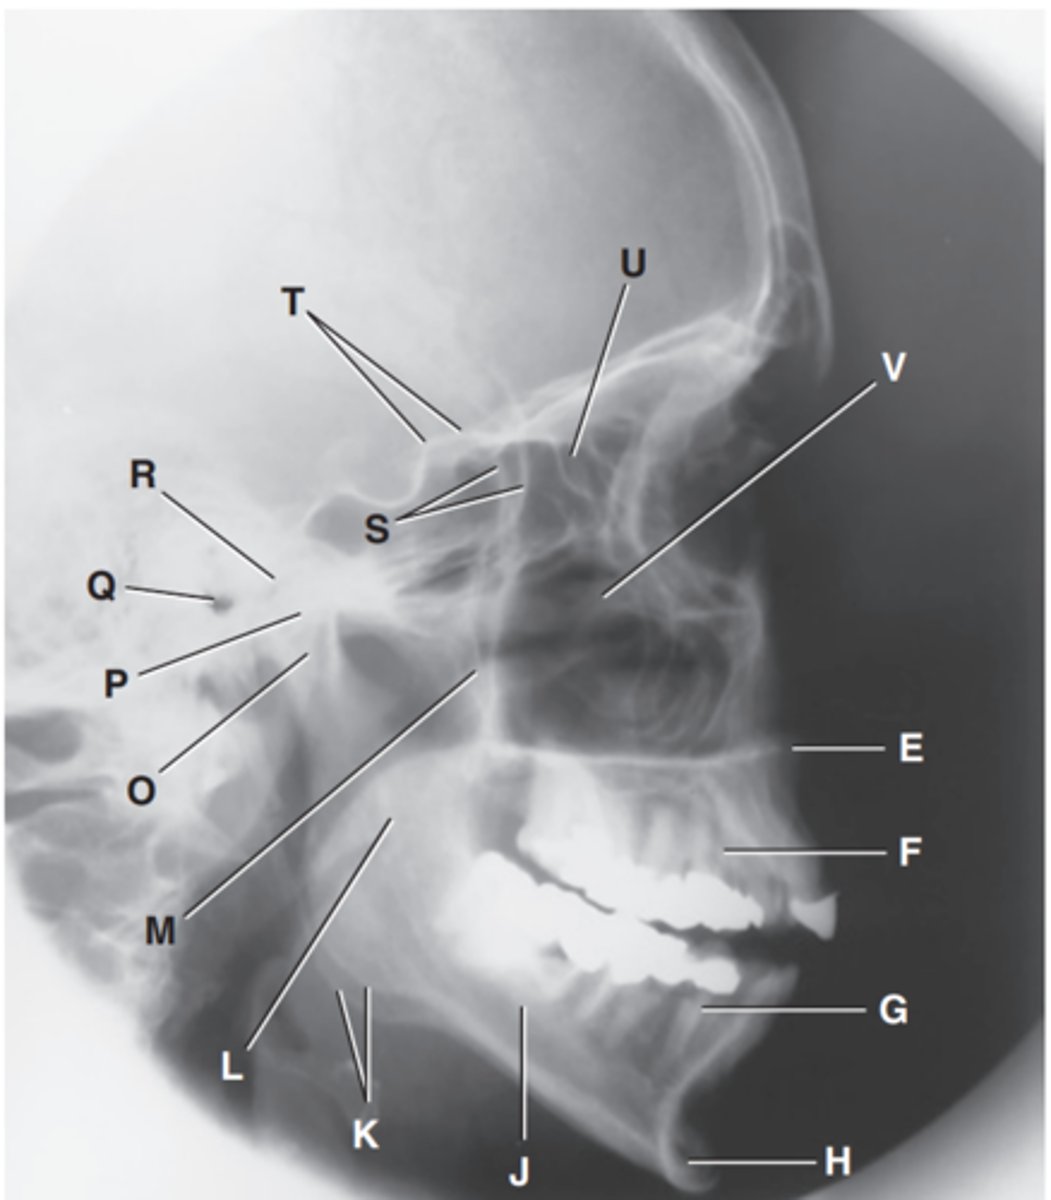

Zygomatic arch

Label A

Right zygomatic bone

Label B

Right nasal bone

Label C

Frontal process of right maxilla

Label D

Anterior nasal spine

Label E

Alveolar process of maxilla

Label F

Alveolar process of mandible

Label G

Mentum or mental protuberance

Label H

Mental foramen

Label I

Body of mandible

Label J

Angle (gonion)

Label K

Ramus of mandible

Label L

Coronoid process

Label M

Mandibular notch

Label N

Neck of mandibular condyle

Label o

Condyle or head of mandible

Label P

EAM

Label Q

TM fossa of temporal bone

Label R

Greater wings of sphenoid

Label S

Lesser wings of sphenoid with anterior clinoid processes

Label T

Ethmoid sinuses between orbits

Label U

Body of maxilla containing maxillary sunuses

Label V